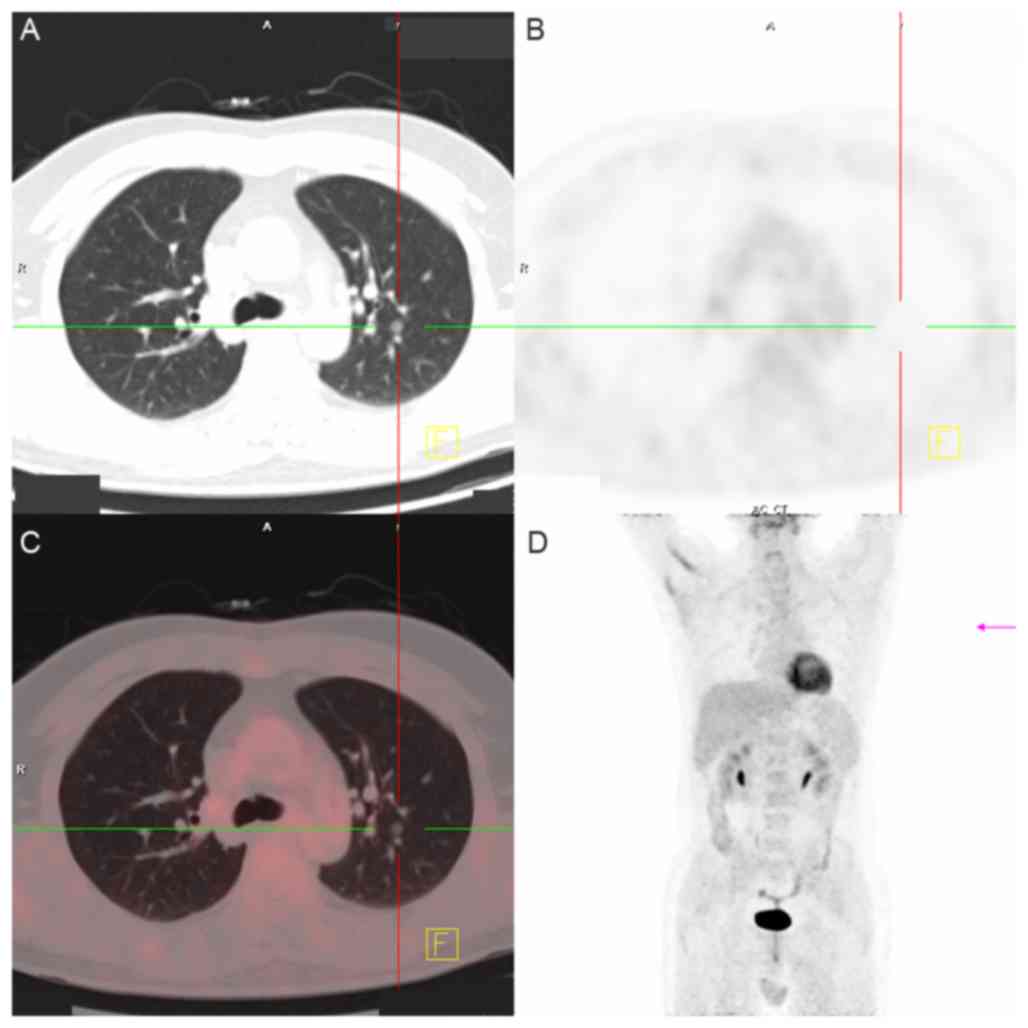

Figure 4.

Positron emission tomography-CT images of GGN in the left lung at admission. (A) CT image, the left upper lobe exhibited one GGN. (B) Functional metabolic image, indicating that nodules have no metabolism. (C) CT and metabolic fusion image. (D) Functional metabolic image. CT, computed tomography; GGN, ground-glass nodule.